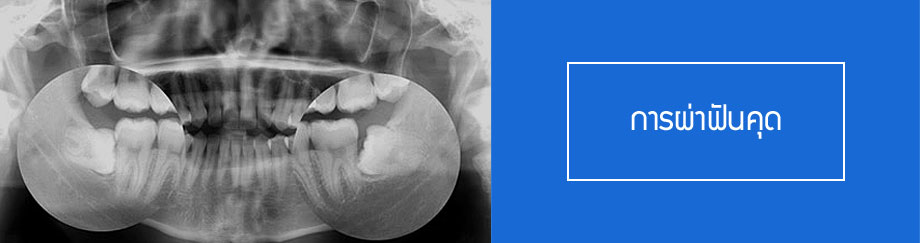

1. การผ่าตัดเพื่อผ่าฟันคุด

ฟันกรามซี่สุดท้ายที่เรียกว่าฟันคุดนั้น เป็นฟันชุดสุดท้ายที่จะออกมาตอนช่วงอายุระหว่าง 18 – 20 ปีซึ่งใน

ความเป็นจริงฟันชุดนี้ก็มิได้มีความแตกต่างจากฟันซี่อื่นๆเพียงแต่น้อยคนนักที่มีฟันกรามขึ้นมาตามปกติพร้อมกับมีตำแหน่งลักษณะการขึ้นที่เหมาะสมและมีเหงือกโดยรอบที่มีสุขภาพดี เมื่อไหร่ก็ตามที่ฟันกรามซี่ในสุดมีอุปสรรคใน การขึ้นอาจเนื่องจากลักษณะการงอกออกมา หรือปัญหาทางด้านอื่นเรียกว่า “ฟันคุด” ซึ่งทันตแพทย์จะทำการเอ็กซเรย์ดุลักษณะและตำแหน่งการวางตัวของฟันวิเคราะห์ถึงความผิดปกติก่อนทำการวางแผนรักษา